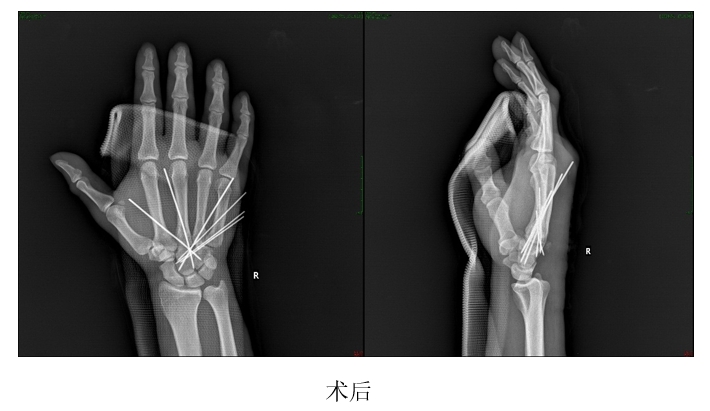

张先生在国外时意外碰伤右手,造成右手第2-5腕掌关节脱位合并多处腕骨骨折和韧带损伤,在当地医院多次尝试复位,均未能成功,由于损伤严重,大量出血,肢体肿胀严重,张先生寝食难安,精神萎靡。经朋友联系介绍,张先生返回国内,来到我院郑州院区手外显微骨一科就诊。反反复复的复位、长时间的飞行进一步加重了张先生患肢的肿胀,在到达我院郑州院区的时候甚至出现了手指没有感觉的症状。赵治伟主任判断,这是骨筋膜间室综合征的表现,如果任其发展,张先生患者可能要面临肢体坏死甚至是截肢的风险。于是,赵治伟主任迅速组织科室人员,为这位患者开辟绿色通道,安排了急诊手术。经过积极地治疗和精心护理,患者目前恢复良好。

赵治伟主任说明:“在处理骨折和脱位的同时,必须警惕骨筋膜间室综合征的发生,这是非常严重的创伤急性并发症,治疗的关键在于预防,一旦错过最佳治疗时机,将会造成肢体坏的严重后果。这位患者是幸运的,历经3天,辗转近1万公里,最终得到及时救治。患者不远万里来到我院,我们一定不能辜负患者的信任,祝愿他早日康复。”